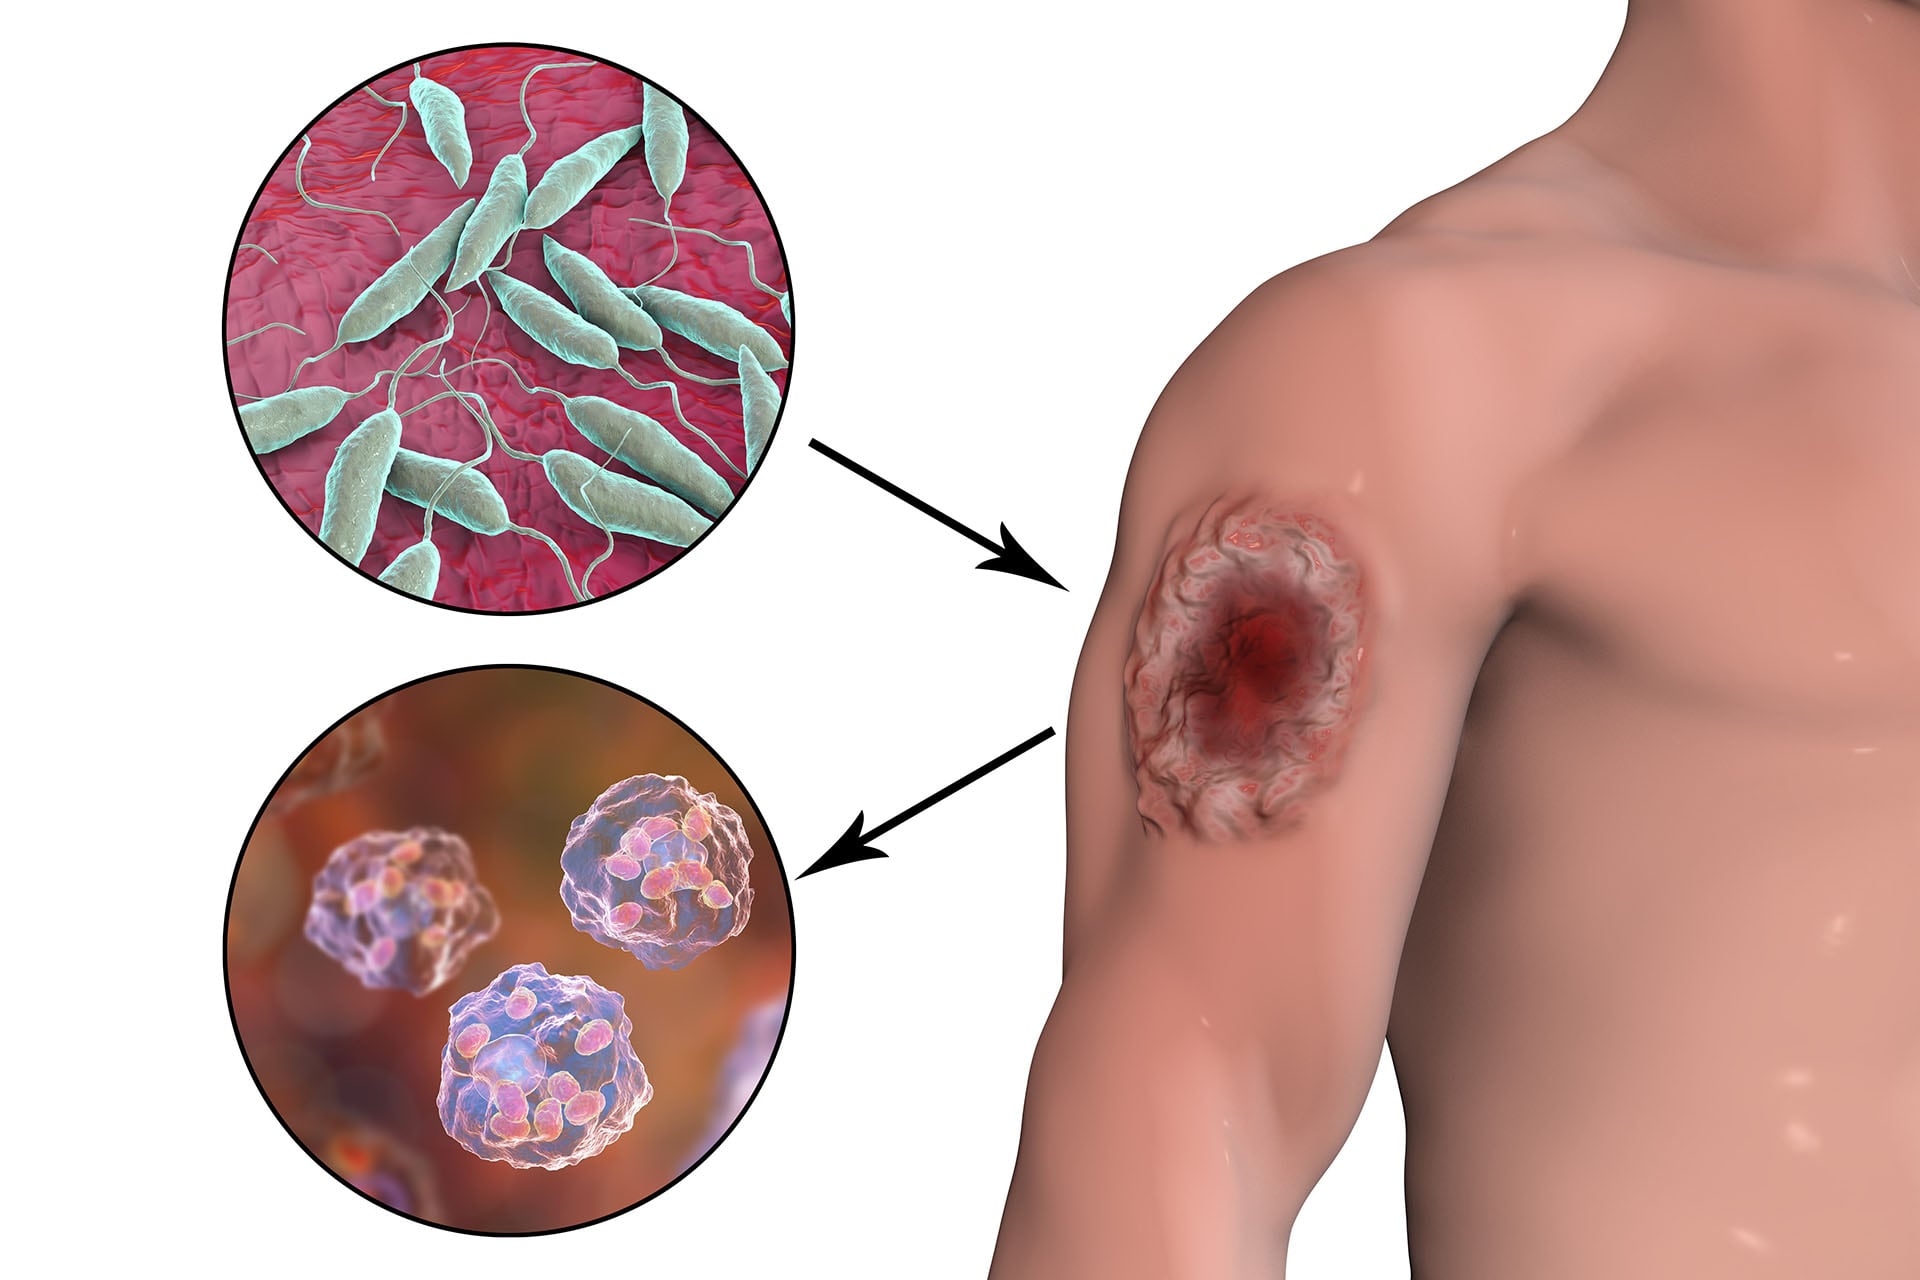

El informe del Minsa también reporta un aumento en los casos de leishmaniasis, con 537 casos acumulados en lo que va del año, lo que refleja una tendencia al alza en esta enfermedad parasitaria transmitida por la picadura de insectos.

La leishmaniasis es causada por parásitos del género Leishmania y se manifiesta principalmente en la piel, generando úlceras que pueden dejar cicatrices permanentes. Sin embargo, en su forma más grave, conocida como leishmaniasis visceral, puede afectar órganos internos como el hígado y el bazo, comprometiendo la vida del paciente si no se trata a tiempo.